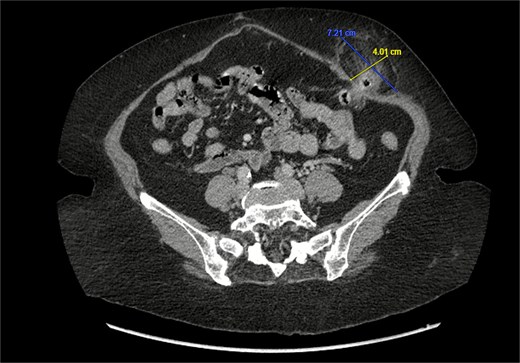

A 76-year-old female with a medical history of type 2 diabetes mellitus (controlled with oral medications), hypertension (on two medications), hyperlipidemia (on atorvastatin), and recently diagnosed Alzheimer’s disease (started on memantine) presented to the emergency department with severe left-sided abdominal pain of 2 days’ duration. The pain began gradually but worsened significantly in the last few hours. It was associated with a bulging mass in the abdomen that was tender and painful to touch. The patient reported that the swelling had been present for 2 years, intermittently reducible with minimal exertion. However, since the previous day, it had become irreducible and increasingly painful, particularly after a failed attempt to reduce it manually at home. She also admitted to chronic constipation for years, usually treated with oral laxatives, though she had not been compliant with them recently. Her surgical history included a laparoscopic cholecystectomy combined with paraumbilical hernia repair using mesh 3 years ago. Upon examination by the on-call surgical team, the patient was afebrile with stable vital signs. Her abdomen was distended, and a 7 × 7 cm irreducible, tender mass was noted over the left side. An urgent computed tomography (CT) scan of the abdomen and pelvis with intravenous and oral contrast revealed a left lateral ventral abdominal hernia traversing the left lateral oblique muscles. The hernia sac contained omental fat and an inflamed diverticulum of the transverse colon, with surrounding inflammatory changes. The defect measured 1.4 × 1 cm, and the hernia sac measured 6.7 × 4.2 × 4 cm. No free fluid, fluid collections, or pneumoperitoneum were identified (Figs 1–3).